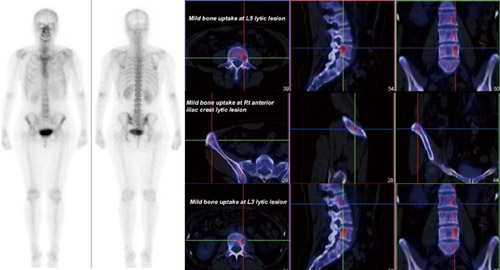

SPECT・CTで描出できた症例